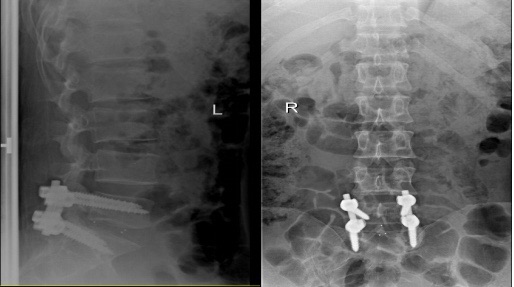

外地来沪工作的方先生(化名)今年30岁,是一名建筑设计师,工作很忙,经常加班,下工地等。有一天,他隐隐感觉右腿痛,行走有些困难,但没太在意,两天后下班回到宿舍方先生感觉右腿痛严重了,休息一晚没有好转,第二天,他到附近一所大医院去看门诊,拍了右腿、右膝的X光片,没有发现问题,开药后,回家休息。 又过了一天,方先生的右腿剧痛,下不了床,且翻身困难。同事送往上海德济医院急诊,德济医院骨科当值医生询问病史,并进行查体后,判断方先生是右侧坐骨神经痛,当即安排腰椎核磁共振检查。核磁共振检查结果:腰5骶1椎间盘偏右侧突出,伴部分髓核脱出,相应的神经根显示不清,于是立即安排住院。方先生和家人非常感激德济的医生为他明确了诊断。 上海德济医院骨科何博主任向方先生一家阐述了手术治疗的必要性。腰椎间盘突出症虽然大多时候属于慢性疾病,但方先生这例属于腰椎间盘突出症急性发作,神经压迫的症状体征非常典型,保守治疗的意义不大,还可能造成更严重的后果,需要外科手术干预。 方先生和家人多方咨询并且百度了各种手术方式优缺点。最终决定手术治疗,并为杜绝复发的可能,要求同时做融合术。 骨科何博主任、刘春主任带领手术团队周末加班为方先生行“腰椎间盘突出髓核摘除,cage植入,椎弓根螺钉固定术”。手术非常顺利,方先生说:术后当天就感觉右腿就明显疼痛减轻,可以抬起了。方先生术后第二天就下床活动,从外地赶来的父母对德济医院骨科团队非常感激!

△术后影像图